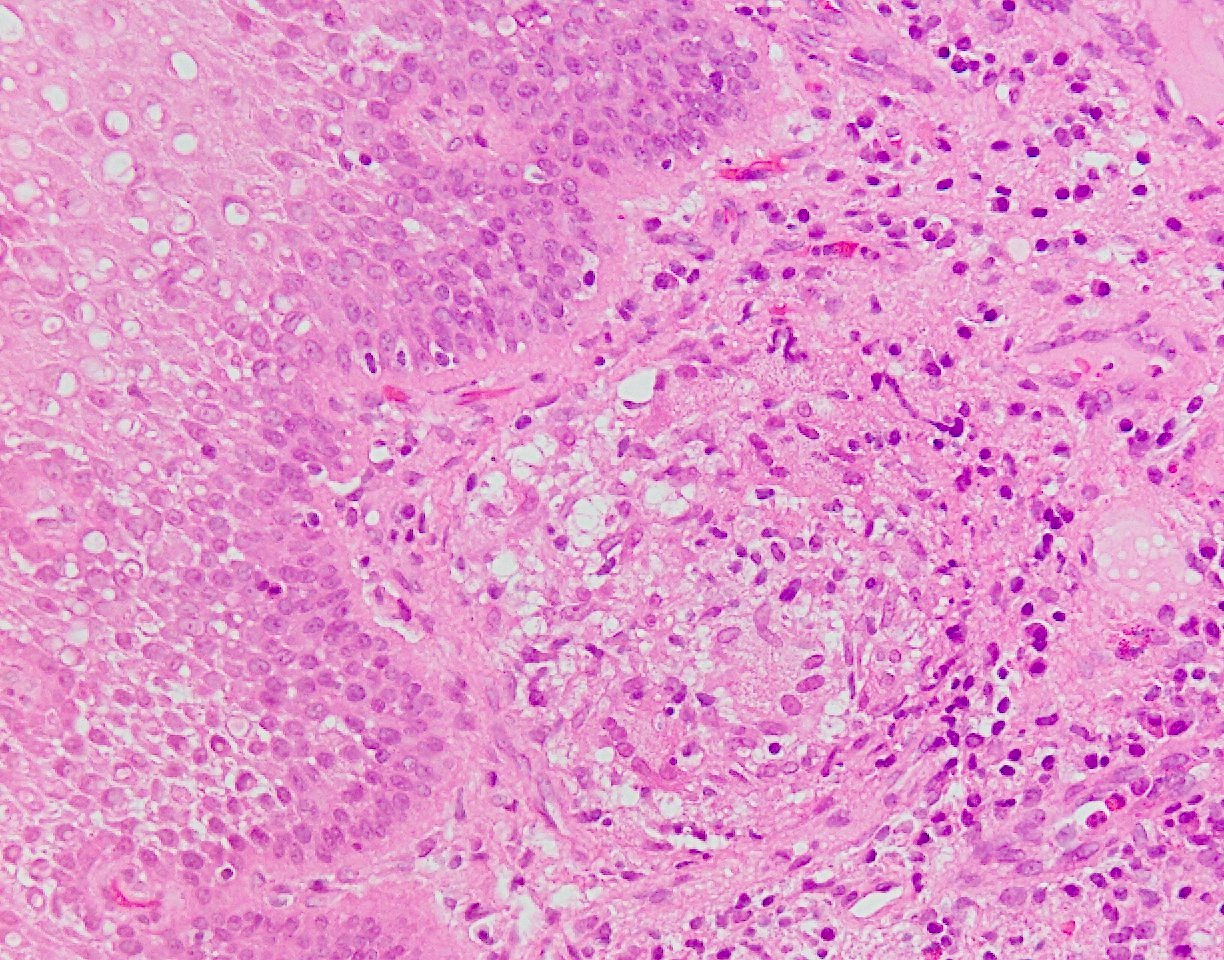

(A) Esophageal Crohn's disease (magnification 20x). Presence of an... Download Scientific Diagram Crohn's Disease Esophagus Crohn's disease is a chronic inflammatory condition that affects the gastrointestinal tract. Crohn’s disease (cd) is an idiopathic inflammatory bowel disease that can. We aimed to report the clinical,. Learn how to use biomarkers, select drug. Crohn’s disease (cd) is a heterogeneous disorder with a multifactorial. Esophageal crohn's disease (cd) is challenging and often a disabling phenotype of disease. Crohn's. Crohn's Disease Esophagus.